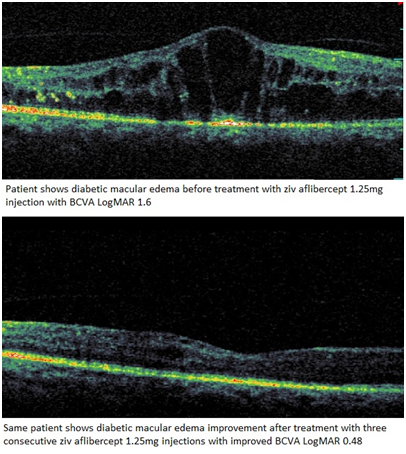

The study has enrolled 10 eyes in 8 patients 4 men and 4 women with mean age 57,9±9,2 years’ Table 1 shows summarized baseline characteristics, all patients received intravitreal ziv-aflibercept every 4 weeks for three consecutive injections. According to (Table 2) there is no significant change in IOP follow up from baseline where best corrected visual acuity was converted from Snellen to LogMAR for statistical analysis, The LogMAR improved from 0.77±0.3 (20/120) at baseline to 0.35±0.2 (20/45) at 12 weeks follow up (P=0.03) Figure 1 shows visual acuity outcome from baseline at 12 weeks follow up; Where CRT was decreased from baseline of 562.4±167.14 µm to 317.7±115.83 µm to 12 weeks follow up (P=0.03), 56.40% is the overall decrease in CRT, (Figure 2) reduction of central retinal thickness from baseline to 12 weeks follow up (Figure 3).

Figure 3 Shows OCT of a patient with DME before and after the treatment with Ziv aflibercept 1.25.

Changes of mean BCVA (P<0.05) and CRT (P<0.05) after the treatment where reduction of 0.42 in BCVA and 244.7 in CRT are noticed in Table 2, Figures 1&2.

However, one of the eyes that have been enrolled in this study presented with diabetic macular edema and epiretinal membrane has shown neither clinical significant visual improvement nor reduction of central retinal thickness. There was no evidence of intraocular inflammation nor toxicity or cataract progression neither systemic complication due to intravitreal injection of Ziv-Aflibercept.